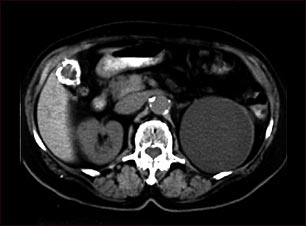

Quiste renal con cálculos biliares; TC

TC del abdomen superior mostrando un quiste del tamaño de un puño en el riñón izquierdo y cálculos biliares (el quiste del riñón se encontró por casualidad; no habían síntomas).